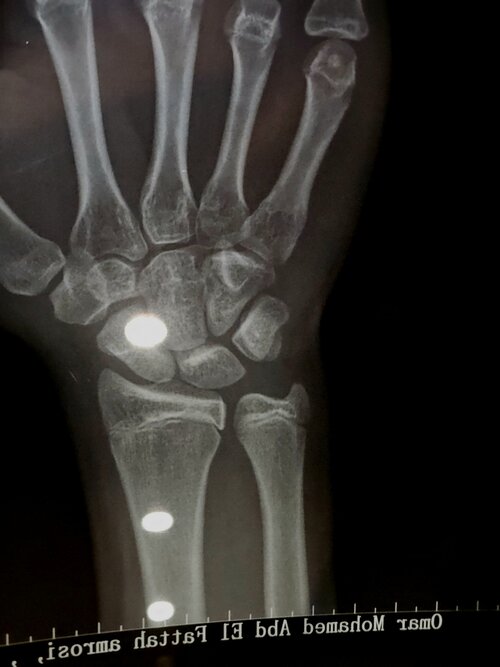

These were my growth plates 1 or 2 weeks ago. @Genio told me its over and that ai wouldnt do nothing since they r fusing this month. But im so fucking desperate. My E2 is already pretty low and under 24 pg/ml and during the day i experience knee pain and finger pain whilst typing. I wanna go lower so bad i wanna grow. HGH wont do shit for me im already 17 very soon and i donnt have the money for it and my parents know everything im getting monitorized nigga.

I beg you for an answer since my time is running out. My calculated bone age is 5 months older than me (based on my calculations)

dont make me cry :( but there are like little lines they are clearly not closed but also not open but i dont think

Still open but very late stage. If your serious then get x rays of both of your tibia and femur plates on both legs. HGH is not expensive btw

I saw your xray from 6 months ago ans it seems the wrist hasnt increased in age alot, how is ur growth velocity?

I grew 1 cm I think in the past months that’s why I thought about ai. In the past 3 months about 1 cm

Your wrist isnt fused yet from the xray. If u start high dose gh+ai u might grow 1-2cm max but it depends on your knee growth plates.